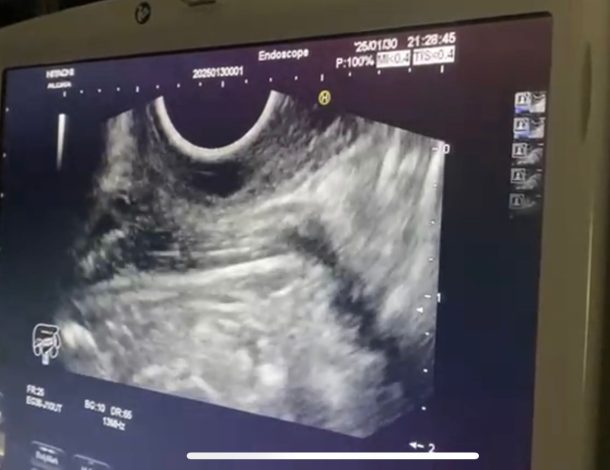

نجحت وحدة المناظير بكلية الطب جامعة حلوان في إجراء أول عملية من نوعها باستخدام منظار الموجات فوق الصوتية لتشخيص واستئصال ورم بالمريء في جلسة واحدة، دون الحاجة لإجراء فتحات جراحية، وذلك بمستشفى بدر الجامعي.

وتمت العملية في غضون 30 دقيقة باستخدام تقنية مناظير الفراغ الثالث، حيث تم تحديد نوع الورم ومكانه وحجمه ومنشئه عبر منظار الموجات فوق الصوتية، ثم استئصاله مباشرة في نفس الجلسة. وتميزت العملية بتوفير الوقت على المريضة وتجنيبها مخاطر التخدير المتكرر، حيث تم خروجها من المستشفى خلال 24 ساعة في حالة صحية ممتازة دون أي مضاعفات.

أجريت العملية تحت إشراف الدكتور شريف البحيري، مدرس الباطنة العامة بكلية الطب واستشاري المناظير التداخلية ومناظير الفراغ الثالث، والذي تلقى تدريباً متخصصاً على هذه التقنية المتقدمة في جامعة كاتب أتاتورك بتركيا خلال مهمة علمية من جامعة حلوان.